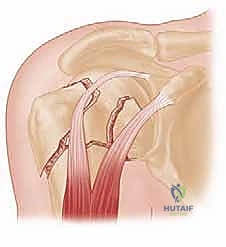

التشريح الحيوي لمفصل الكتف وعظم العضد القريب

لفهم طبيعة الكسر وكيفية علاجه، يجب أولاً فهم التشريح المعقد لمفصل الكتف. يُعتبر مفصل الكتف المفصل الأكثر حرية في الحركة في جسم الإنسان، وهذا المدى الحركي الواسع يأتي على حساب الاستقرار، مما يجعله عرضة للإصابات.

يتكون عظم العضد القريب (الجزء العلوي من عظم الذراع) من أربعة أجزاء رئيسية تشريحياً:

1. الرأس المفصلي (Articular Head): الجزء الكروي الذي يتمفصل مع التجويف العنابي للوح الكتف.

2. الحديبة الكبرى (Greater Tuberosity): نقطة اتصال العضلات المدورة للكتف (Rotator Cuff) من الأعلى والخلف.

3. الحديبة الصغرى (Lesser Tuberosity): نقطة اتصال العضلة تحت اللوحية من الأمام.

4. الجدل أو العنق الجراحي (Surgical Neck): المنطقة الأضعف تحت الرأس والحديبات، وهي الموقع الأكثر شيوعاً للكسور.

الخطر الأكبر في كسور هذه المنطقة هو تأثر التروية الدموية (الإمداد الدموي). الشرايين التي تغذي رأس عظم العضد دقيقة جداً وأي تمزق فيها قد يؤدي إلى حالة خطيرة تُعرف باسم "النخر اللاوعائي" (موت أنسجة العظام بسبب نقص الدم). وهنا تبرز عبقرية تقنية التثبيت عبر الجلد التي تحافظ على هذه الأوعية الدموية الحساسة.